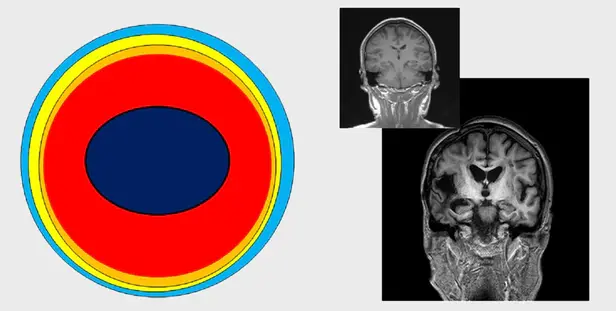

A-B 주관적인지장애를 겪는 사람의 뇌 상태. 촬영 사진만 보면 정상 뇌와 거의 차이가 없다. 그러나 이후 경도인지장애와 치매로 진행되면서 뇌의 모습이 확연히 변한다.

B-C 경도인지장애

C 치매의 뇌 상태

“몇가지 이유가 있다. 첫째, 너무 늦게 발견된다. 현대 의학은 객관적 근거가 있어야 병으로 진단한다. 예를 들어 MRI(자기공명영상)나 인지기능 검사를 통해 이상이 발견되어야 치매로 진단한다. 그러나 이런 방식으로 치매가 발견되었을 때에는, 대표적인 치매인 알츠하이머의 경우를 예로 들어 말하자면 알츠하이머치매 진행 7단계 중 4단계로 진행된 상태이다. 치매라고 진단을 받으면 많은 뇌세포가 이미 죽었거나, 제 기능을 못하는 좀비 상태이다. 더구나 MRI 촬영을 하면 죽은 세포 집단은 위축된 상태로 화면에 나타나지만 좀비세포 집단은 정상세포 집단과 구별이 잘 되지 않는다. 그래서 치매의 진단이 어렵다.